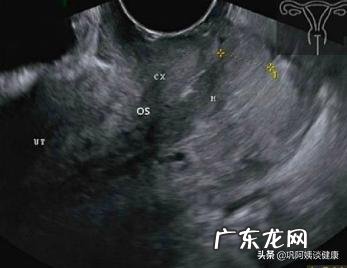

病例一(见图1.2)

患者女,46岁 。主诉:经期延长淋漓不尽约半年,要求体检 。G2P1,人工流产1次,足月顺产1胎 。平时月经周期正常,经量偏多,偶有性交后阴道少量出血,余无不适 。

妇科检查:宫颈外口处突出宽约1cm指状实质性赘生物,白带清洁度Ⅲ度,霉菌检查(-),滴虫检查(-),HPV(-) 。

超声检查:子宫前位,子宫内口和外口及颈管都分离,颈管黏膜层前后分离清晰连续,颈管及宫腔内有立体感呈圆柱形低回声团块,根部位于子宫宫腔中段前壁肌层,穿过内口通过颈管一直延伸落出子宫外口,大小1.1cm×1.3cm×5.2cm,CDEI示团块周围环状血流特征 。

超声提示:子宫宫腔颈管内赘生物(子宫黏膜下肌瘤可能) 。

宫腔镜手术摘除赘生物,病理检查:子宫黏膜下肌瘤 。